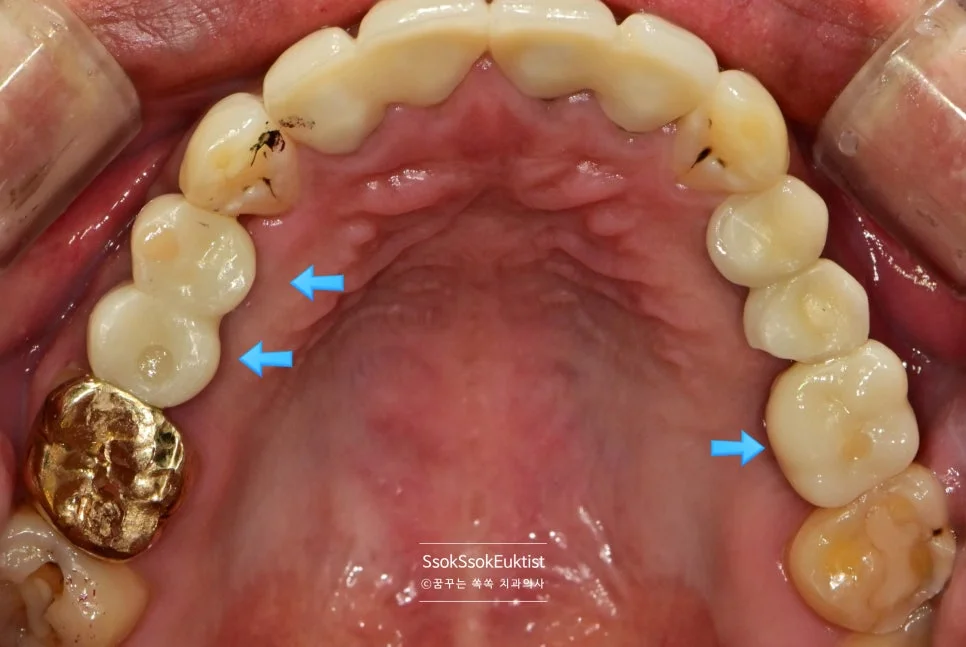

2차 수면 마취 — 우측 임플란트 3개 식립 완료 (화살표)

가능한 주변 골보다 2~3mm 깊게 임플란트가 온전히 뼈 안에 잠기게 식립되었다면 잘 심긴 임플란트입니다.